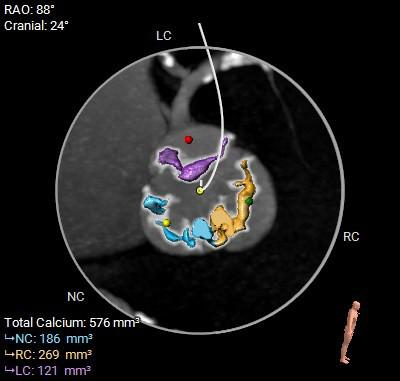

在完成术前CT扫描后发现,李阿姨入路腹主动脉严重扭曲、横位心、右冠窦无冠窦钙化融合且冠脉开口位置相对较低,左冠瓣叶冗长,术中冠脉闭塞风险高,这些不利因素均会明显增加手术的难度和风险。为此,医院迅速启动多学科协作机制,由医务处牵头,联合心血管科、麻醉科、重症医学科、血管外科、胸外科等专家团队展开会诊。经过反复讨论,专家团队最终决定采用国际先进的治疗方案一一经导管主动脉瓣置换术(TAVR)。这种微创手术无需开胸,只需通过血管穿刺即可完成瓣膜置换,极大降低了手术风险。为确保万无一失,心血管科团队还通过线上会议邀请国内知名专家对病例进行远程讨论,制定了精细化手术方案,包括入路解决方案、冠脉保护策略、术中应急措施以及术后康复计划。

▲术前CT评估

患者病理特点

1. 冠脉高风险:三窦三叶式主动脉瓣,右无之间钙化融合,钙化分布不均。右无融合脊会把瓣架往左冠脉开口方向推挤,并且左冠瓣叶相对冗长,大大增加了冠脉阻挡的风险。